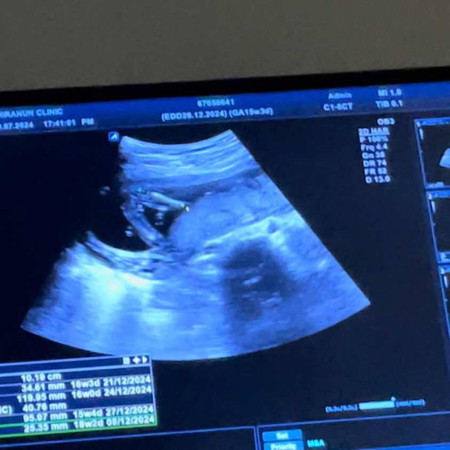

แบบนี้เพศ หญิงหรือชายคะ หมอบอกยังแฟบยุ่ยังไม่ชัวร์อายุครรภ์ยังน้อยด้วยค่ะ15+4 แม่ๆคิดว่าเพศอะไรคะ